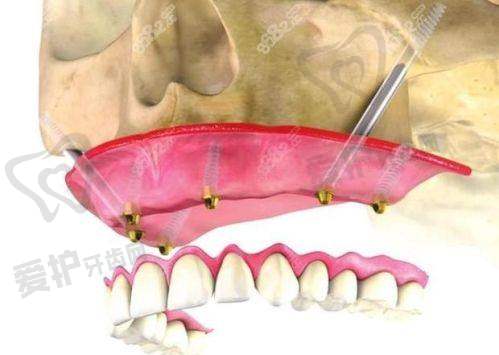

穿颧穿翼半口种植牙是一种针对重度骨量缺失患者的高端种植技术。传统的种植牙技术需要患者有足够的牙槽骨骨量来支撑种植体,但对于一些因长期缺牙、外伤等原因导致牙槽骨重度吸收的患者来说,传统种植往往难以实施。而穿颧穿翼种植牙技术则突破了这一限制,它通过将种植体植入颧骨或翼板等骨量充足的部位,为种植体提供稳定的支撑,从而实现半口牙齿的修复。

这种技术的优势十分明显。首先,它避免了传统植骨手术的痛苦和漫长的愈合期,大大缩短了治疗周期。患者可以更快地修复咀嚼功能,提高生活质量。其次,穿颧穿翼种植牙的稳定性更高,能够承受更大的咀嚼压力,使用寿命也更长。对于那些对牙齿功能和美观有较高要求的患者来说,无疑是一个理想的选择。